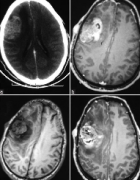

磁共振成像(MRI)是有用的迅速识别这些病理,以避免长期性视力丧失。在T2W图像上,显示中央等强度,周围高强度对应于神经周围蛛网膜神经胶质瘤。图3:...